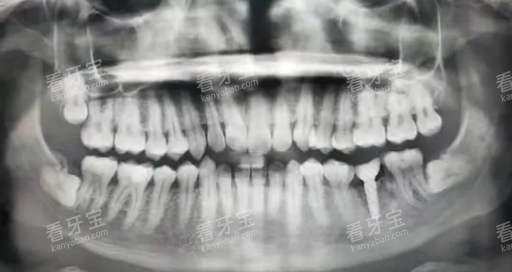

"年轻人,你这颗智齿已经蛀到接近神经了,而且位置不正,清洁确实很困难。我的建议是拔除,虽然听起来可怕,但长远来看对你更好。"

他接着说:"如果你实在害怕,我们也可以先尝试治疗,但你要做好心理准备,这可能只是个临时解决方案。"

看着X光片上那颗歪斜的智齿,我终于下定了决心:"那就拔了吧,长痛不如短痛。"